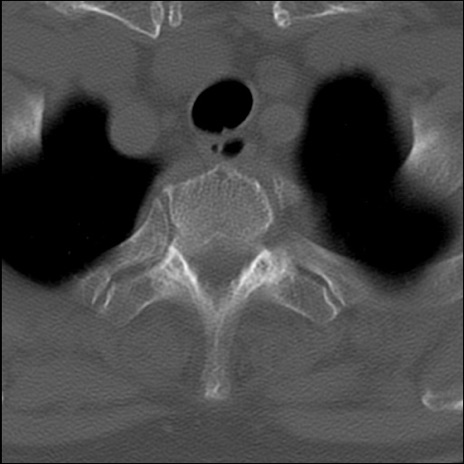

冠状断像